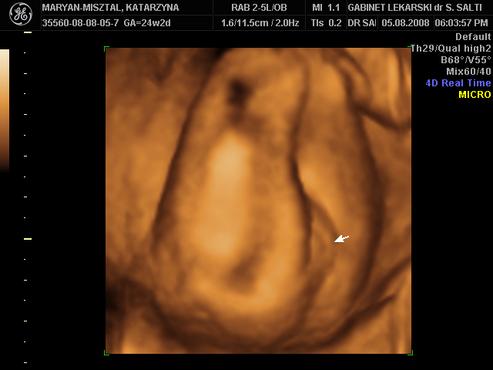

Z dziewczynkami jest faktycznie mniejsza pewnośc, bo "ogonek" moze sie schowac,a ujawni sie dopiero przy porodzie hihi.A jak juz cos zamajda-to wiadomo,że chłopak i pewnośc większa. No ale, jak mi doktor mówi,że widac wyraźnie wargi sromowe(a jest jednym z najlepszych specjalistów od usg w Polsce), to się kłócic nie bedę:-).Załączam fotki-na drugiej zaznaczyłam obrysem pupcię mojej niuni(widok z dołu).No chyba nie powiecie,że to chłopak?!